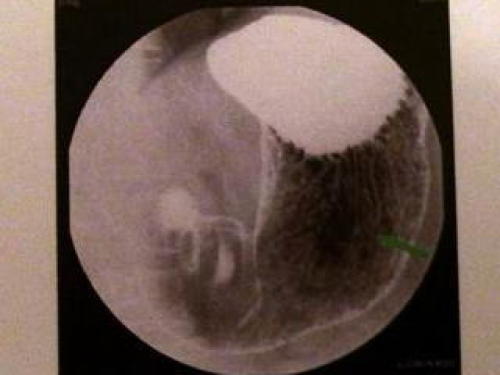

おぉ!画像が印刷されてる!

これが、俺の胃かー。なんて感激してましたが、案の定、

うーん、画像に矢印?ポリープの疑い箇所、要経過観察アゲインです・・・。2年前までは毎年ポリープの疑いを指摘されてましたが、去年は無くなってました。見逃した?治った?なんて喜んでましたが、やっぱりあった。

で、もう1枚の写真。

おー、なんか胃っぽい!